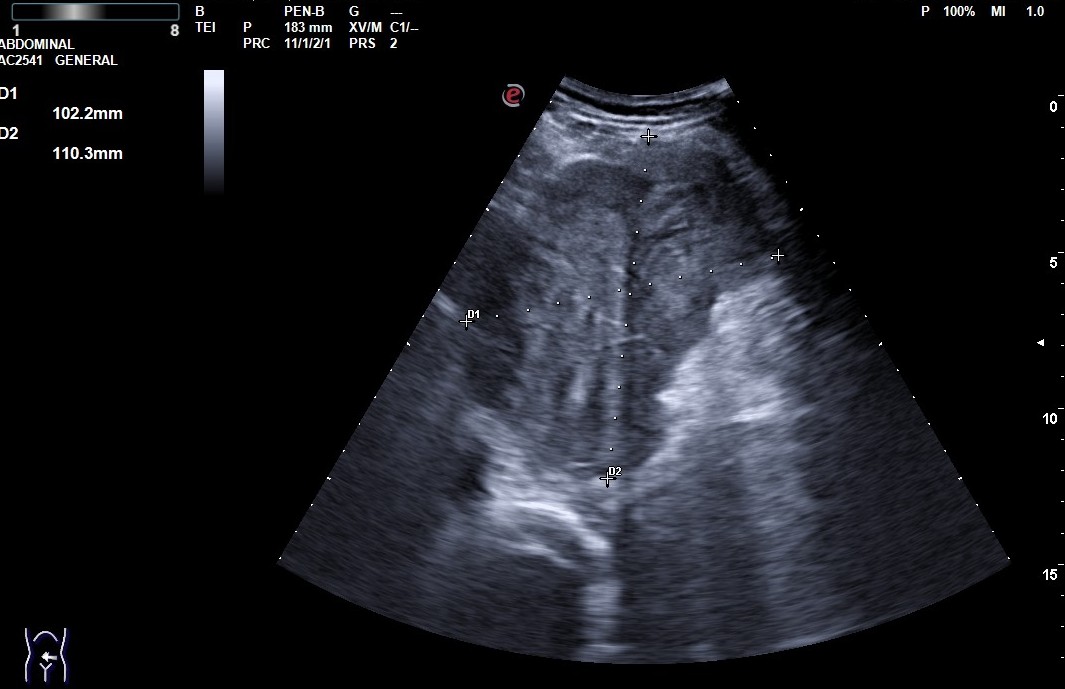

Hallazgos ecográficos

Se realiza ecografía en el Centro de Salud, donde se observa una masa de 123 x 102 x 103 mm de ecogenicidad mixta, con algunas áreas calcificadas en su interior, puntiformes, con bordes lobulados bien definidos, sin captación vascular. Se manda imágenes a Radiología mediante e-consulta y tramitan TAC abdominal, donde se confirma la masa de 12 cm de diámetro, siendo GIST la primera opción diagnóstica, a valorar proceso linfoproliferativo o sarcoma retroperitoneal.